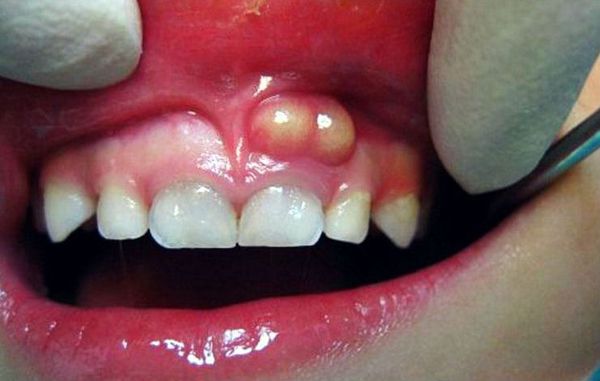

Ostre ropne zapalenie okostnej (stan zapalny błony pokrywającej kość z obecnością ropy) zazwyczaj nie powoduje ograniczenia otwierania ust. Podczas badania palpacyjnego węzłów chłonnych w okolicy zmiany często stwierdza się objawy ostrego zapalenia węzłów chłonnych (powiększenie i bolesność węzłów). Podczas badania jamy ustnej widoczny jest ząb przyczynowy (czyli ten, który wywołał stan zapalny), reagujący ostrym bólem na opukiwanie (perkusję) – z powodu zapalenia w okolicy wierzchołka jego korzenia. W przedsionku jamy ustnej stwierdza się naciek zapalny (zagęszczenie tkanek), bolesny przy dotyku; błona śluzowa nad nim jest obrzęknięta i zaczerwieniona (przekrwiona). Zgodnie z obserwacjami zapalenie okostnej częściej występuje od strony policzka lub wargi, a rzadziej – od strony podniebienia lub języka.